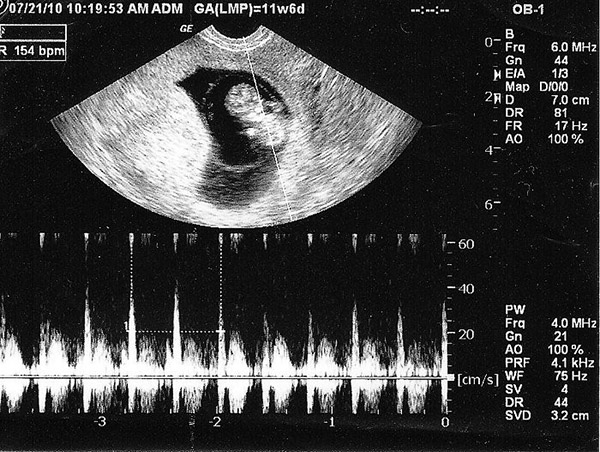

Hầu hết các chi tiết trong bảng kết quả siêu âm sẽ viết bằng tiếng Anh. Vì thế mẹ sẽ cảm thấy khá hoang mang khi cầm kết quả siêu âm trên tay. Sau đây chúng tôi sẽ hướng dẫn bạn đọc một số những chỉ số cơ bản có trong kết quả siêu âm thai 5 tuần:

– GA: Đây được coi là chỉ số biểu hiện số tuổi của thai nhi. Dấu mốc được tính từ ngày đầu của chu kỳ kinh nguyệt cuối cùng cho đến ngày siêu âm.

– GSD: Đây là chỉ số đặc biệt chỉ được biểu hiện trong những tuần đầu của thai kỳ nói lên đường kính túi thai. Khi thai đã bắt đầu hình thành các cơ quan trên cơ thể thì chỉ số này không còn được sử dụng nữa.

– BPD: Chỉ số này sẽ cho biết đường kính lớn nhất tại mặt cắt trên đầu thai nhi, hay còn được gọi là chỉ số đường kính lưỡng đỉnh.

– FL: Chỉ số biểu hiện chiều dài xương đùi của bé

– EFW: Khối lượng thai được ước tính theo máy. Đây là chỉ số quan trọng biểu thị sức khỏe của thai nhi.

– CRL: chỉ số biểu hiện chiều dài đầu-mông. Chỉ số này sẽ ngày càng chính xác hơn vào những tuần cuối của thai kỳ.

Siêu âm thai 5 tuần bác sĩ và mẹ sẽ thấy gì?

Điều thắc mắc lớn nhất của nhiều chị em khi thực hiện siêu âm thai 5 tuần tuổi đó là mẹ sẽ thấy gì. Tuy hình ảnh qua các thiết bị có thể không rõ nét nhưng một số thay đổi đã bắt đầu xuất hiện trên phôi thai mà bác sĩ có thể thấy được như:

– Phôi thai và tim thai: Ở một số bà mẹ có phôi thai phát triển nhanh thì đã có thể thấy được tim thai khi siêu âm thai 5 tuần tuổi.

– Túi noãn hoàng: Khi siêu âm vào giai đoạn này thì có thể bác sĩ sẽ thấy được túi noãn hoàng của thai.

– Túi thai: Túi thai là bộ phận có chức năng bao bọc thai nhi và nước ối. Vì thế khi siêu âm thai 5 tuần tuổi, mẹ sẽ có thể nhìn thấy được túi thai một cách rõ nét.